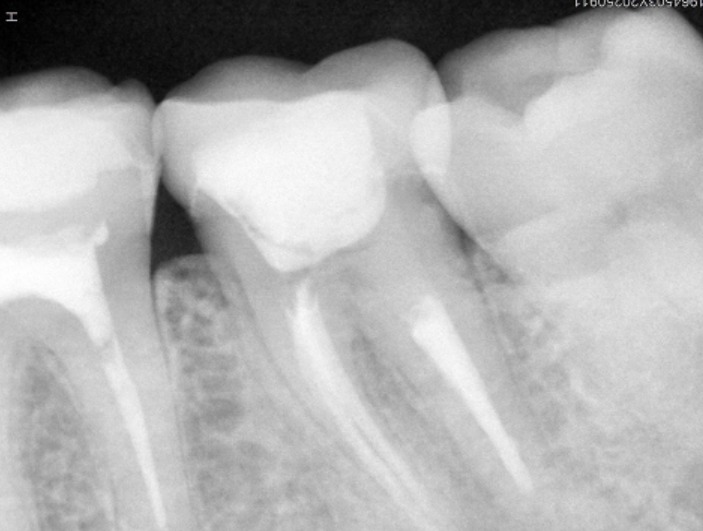

- Radiografía digital para evaluar el caso y controlar cada etapa del tratamiento